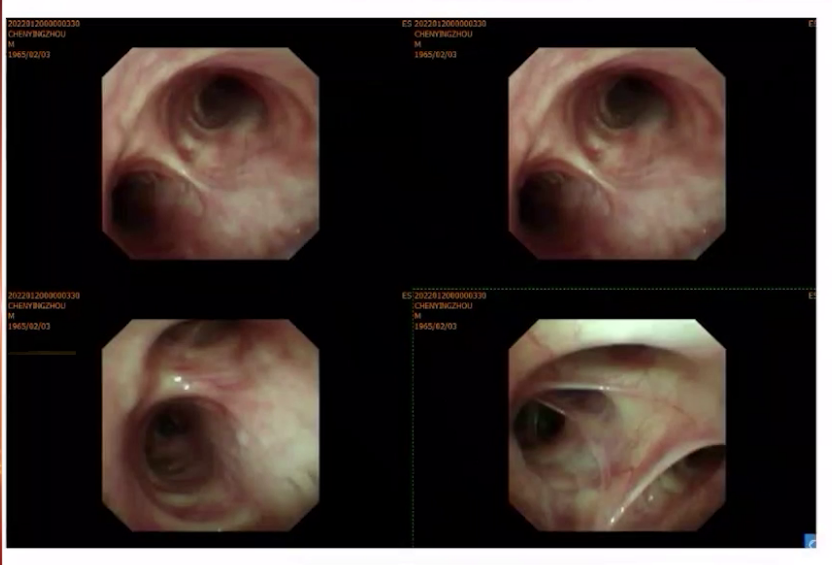

1)气管镜下冷冻活检:支气管镜全麻下经气管插管进入顺利,声门闭合可,气管环清晰,隆突锐利,双侧各叶段管腔通畅,黏膜光整,未见新生物,未见出血,见较多黏痰,予吸除。于左下叶背段灌洗送检查,刷检找结核菌、脱落细胞及液基细胞学检查;左下叶B6行冷冻活检(1.9探头,3秒,2mm直径组织块)。球囊阻塞,出血5ml,止血治疗后好转。

2)BALF:均为阴性。

3)病理结果:(左下叶背段冷冻活检)肺泡间隔增宽伴纤维化,部分区域血管旁见灶性淋巴细胞浸润,特染未见特异性病原体,请结合临床及影像学结果考虑自身免疫相关性间质性肺炎。免疫组化结果:CK (上皮细胞 +),Vimentin(间质细胞 +),LCA(淋巴细胞 +),CD68(组织细胞 +)。特殊染色结果:抗酸(-),六胺银(-),PAS(-),网染(+),偏光(-),真菌快染(-)。结核分枝杆菌基因检测结果:阴性。